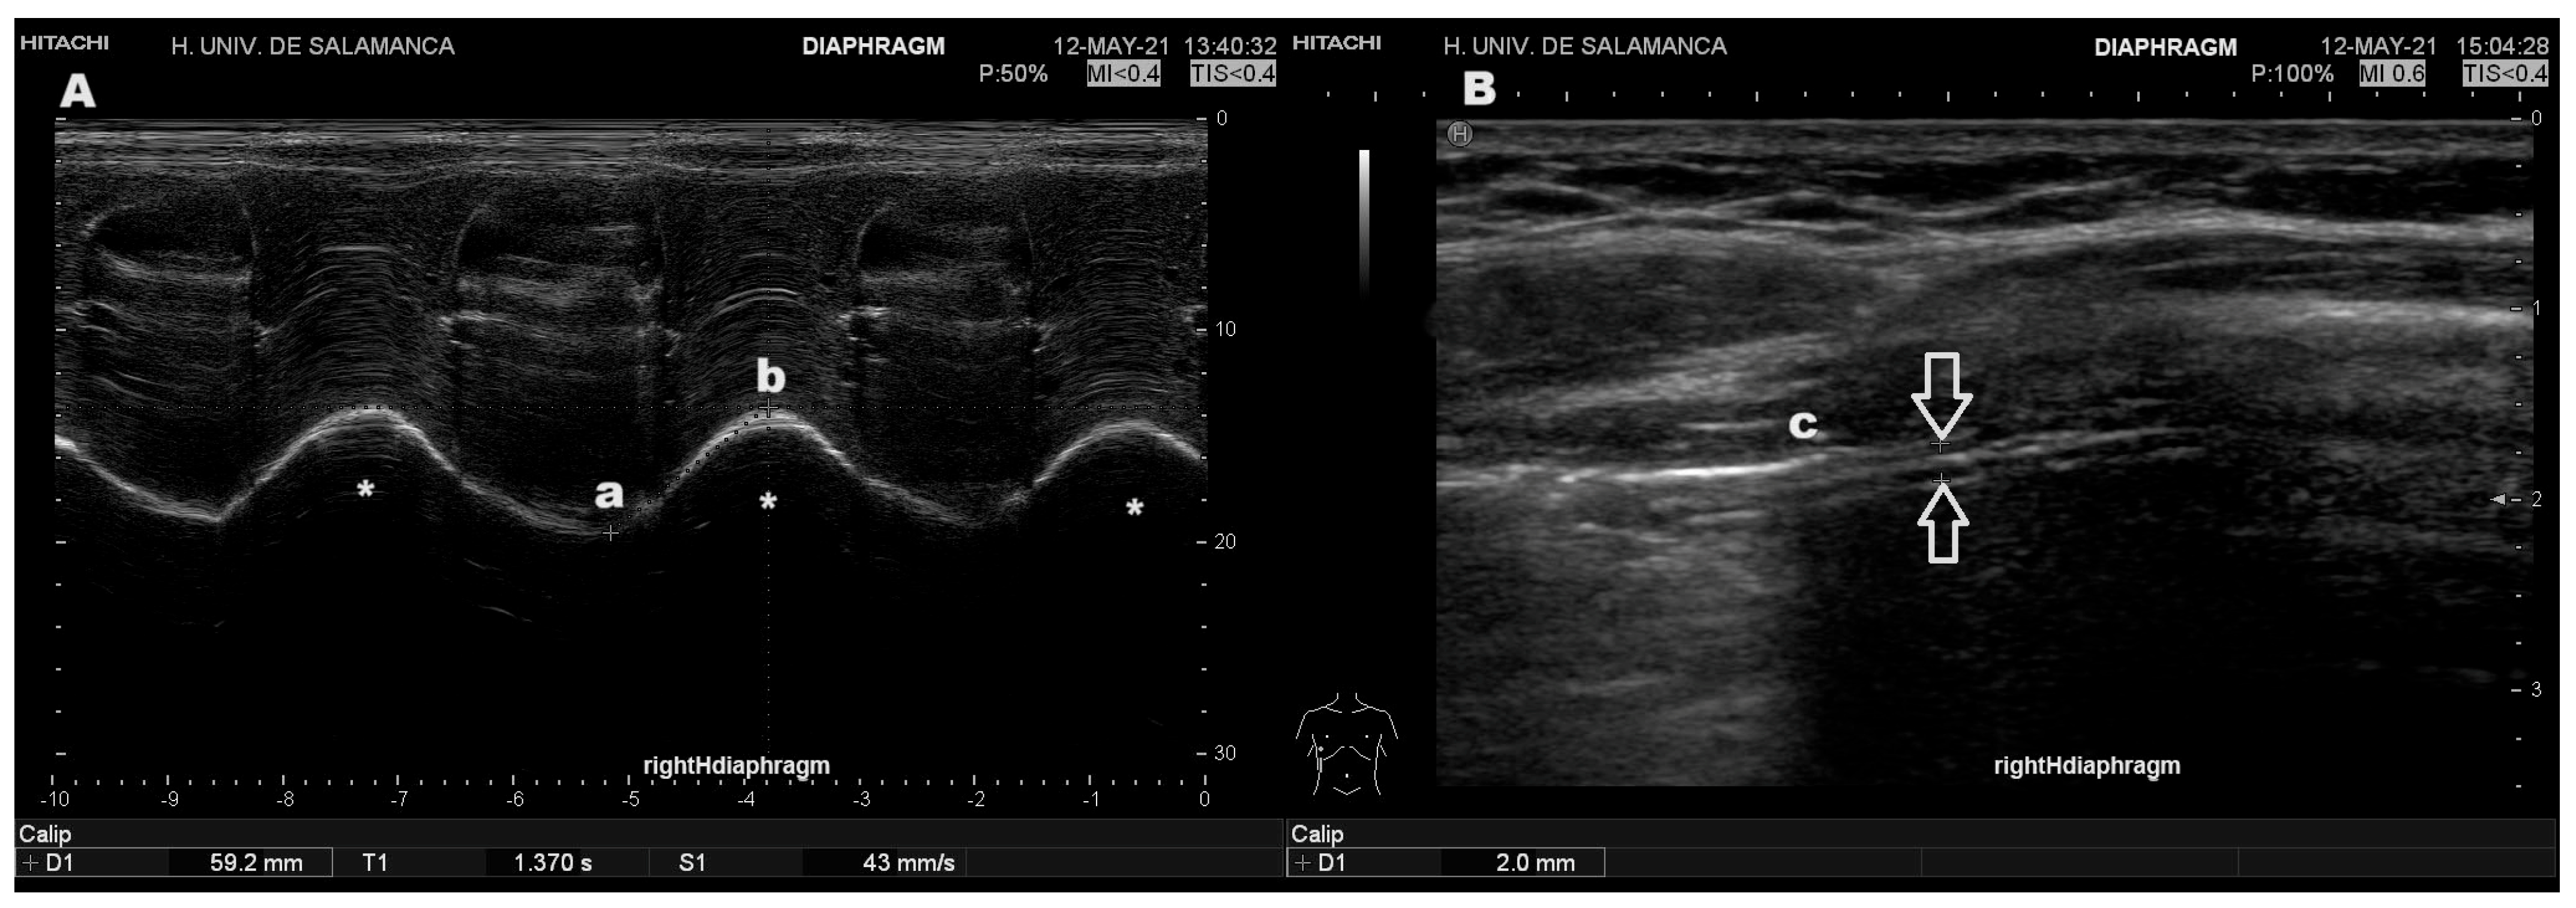

Once this measurement was obtained, the axillary approach was employed, between the 8th and 10th intercostal spaces along the mid-axillary line, bilaterally. After identifying the diaphragm, the segment nearest to its costal insertion was selected during deep inspirations, ensuring the absence of pulmonary parenchymal interference. Subsequently, the rapid and deep inspiration maneuvers were then repeated to obtain the highest values from the hemithorax where these were the highest (Figure 1).

Figure 1. Typical ultrasound images of diaphragmatic ultrasound. (A) Measurement of excursion in M-mode, demonstrating waveforms corresponding to three deep inspirations with waves of three deep inspirations (*). Excursion is measured as the distance between the lowest point at end expiration (a) and the highest point (b) following deep inspiration. Velocity is the relation between that distance and the time to reach the highest point. (B) Measurement of diaphragmatic thickness in B-mode (the diaphragm showed as a sliding three-layer structure between the white arrows), obtained at end inspiration immediately below the inferior lung border (c).